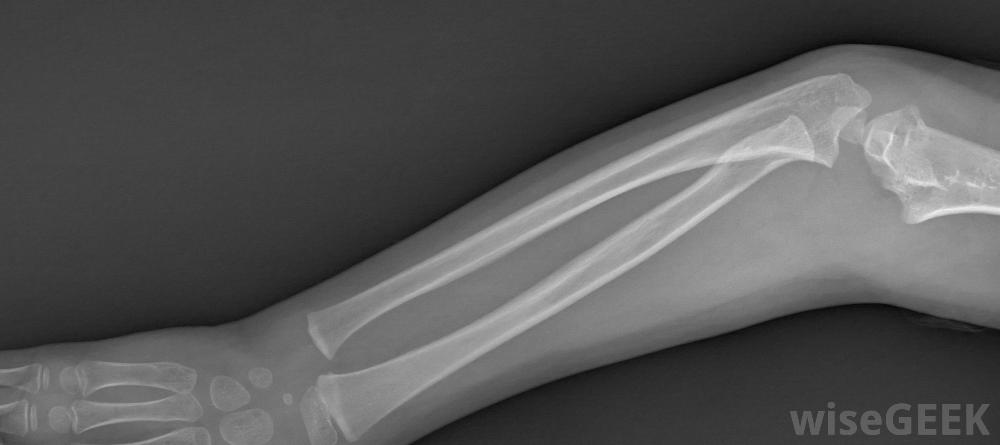

为了选择最好的前臂夹板,你需要评估它能起到什么作用。手腕和前臂的许多损伤都涉及骨折或肌腱拉伤,但并非全部都有。有时损伤不是那么严重,或者是由于慢性问题,如腕管综合征。如果你需要前臂夹板,然而,你几乎总是需要某种保护和稳定的东西。糖钳夹板在前臂骨折中很常见对于需要保护手臂不受电击的损伤,最好的前臂夹板可能是充气的。空气垫通常会将夹板塑造成四肢的轮廓。它还对前臂施加均匀的压力,保持血液循环,另一个优点是前臂空气夹板通常是透明的,这意味着在接受x光检查时可以不使用。但是,它可能会被锋利的物体弹出,而且空气夹板并不总能提供最好的通风前臂夹板通常是透明的,所以在拍x光片的时候就可以不用了。像腕管综合症或者网球肘这样的病症可以用空气夹板来治疗,但也有专门的支架,可用于这些情况下,将允许一些活动,同时保持一些稳定性和保护在肘部也受累的情况下,通常会使用长臂夹板来固定前臂和肘部。如果手指也需要稳定,则会使用专门的前臂夹板。这些夹板有固定手指的附件网球肘患者可能会从气夹板中获益。如果手臂骨折,你可能会得到掌侧夹板或糖钳夹板。夹板通常非常坚硬,由铝、塑料或玻璃纤维制成,并有一个坚硬的金属片来稳定。这些类型的夹板通常从手掌开始,沿着前臂向上,在到达肘部之前停止网球中使用的一些重复动作会给运动员带来很大的压力;前臂肌腱。这种特殊类型的夹板有许多变化。需要考虑的重要因素是易于拆卸和通风。一些前臂夹板完全包裹在手臂上,而其他人则暴露在开阔的地方,用门闩或Velcro®将坚硬的部件固定在适当的位置。Velcro®会更好地呼吸,但门闩可能会提供额外的保护层。如果您需要便宜或简单的东西,并且只有一点点手腕或前臂受伤,使用带Velcro®尼龙搭扣的简单掌侧夹板可能会起作用在前臂上缠上厚厚的布条绷带也能提供轻微的稳定效果,而且通常更便宜,但是它不能呼吸。当你受伤时最好去看医生,以确认损伤的程度,并确保你的前臂夹板适合你的情况肌腱拉伤的患者可以使用前臂夹板。